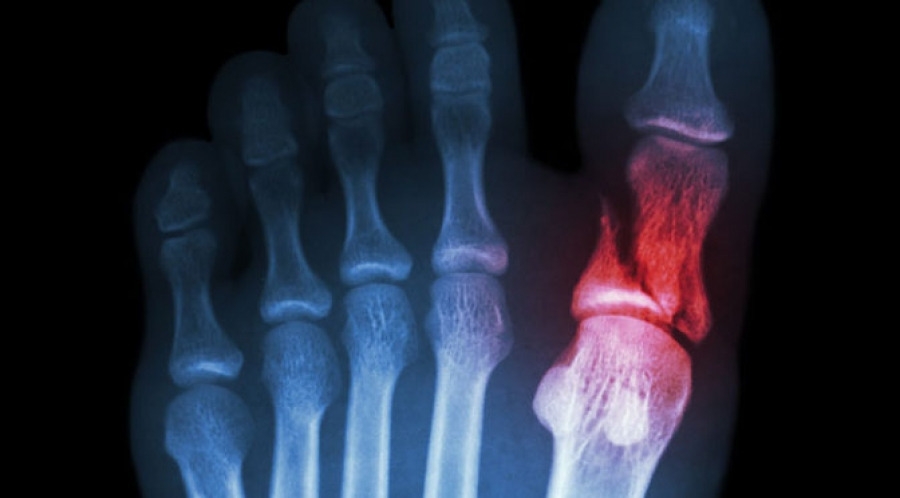

- 국소 부종·멍·감각저하

- 걷거나 디딜 때 통증이 심해짐

- 발가락 변형(휘어짐·각 변위)

- 단순 X선 촬영이 1차

- 불분명하면 CT·MRI로 세부 골절선 확인